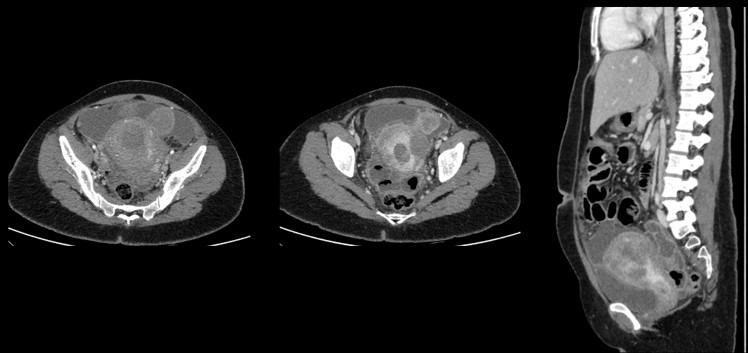

CECT ABDOMEN AND PELVIS - DAY 1

• A. Mild pneumoperitoneum. Few heterogeneously enhancing fibroids seen. Tubular hypodense area in left adnexa - likely pyosalpinx Diffuse greater omental fat stranding and peritoneal thickening - suggestive of peritonitis.

• B. Tubular hypodense area in left adnexa - likely pyosalpinx. Subserosal fibroid in upper corpus.Few loculated fluid pockets with air foci are seen in the pouch of douglas